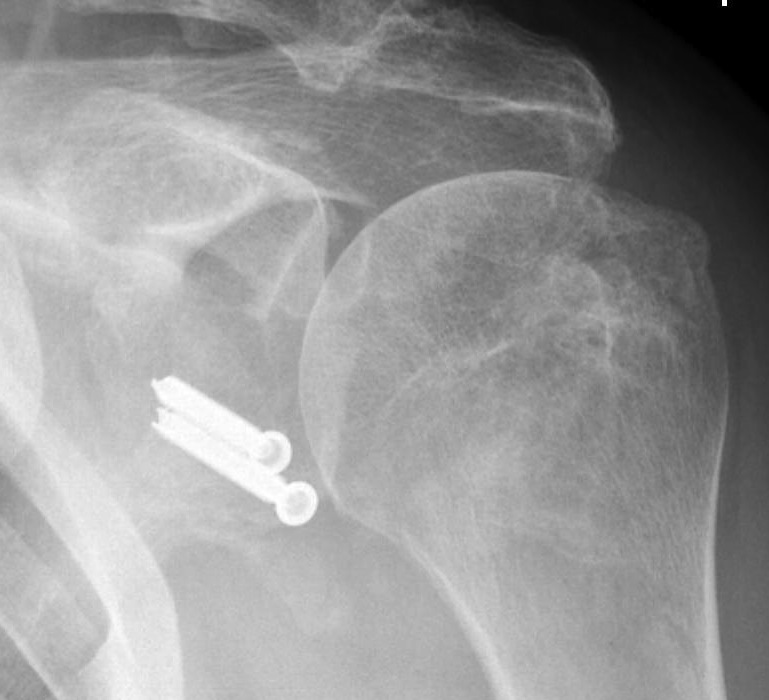

Combined Glenoid and Scapula Fractures

Case 1

- displaced glenoid fracture and neck fracture

- ORIF both through posterior / Judet approach